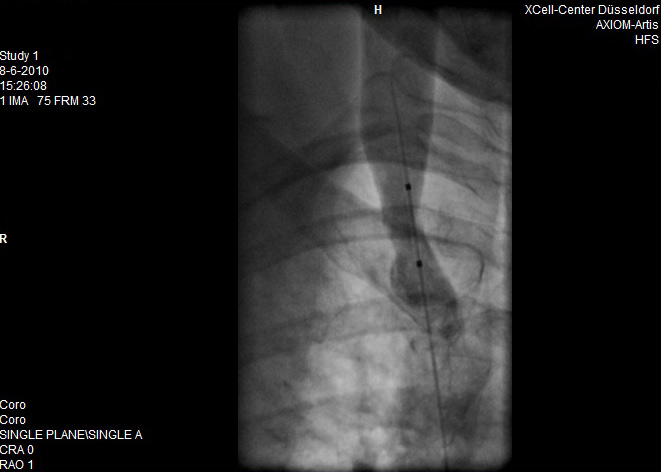

En hier de scans van de behandeling

Opmerkingen bij bestand: Na de behandeling

na.jpg

na.jpg [ 50.2 KiB | 19706 keer bekeken ]

Goed...we zijn nu 24 uur verder.

Ik heb Angeliek weer gefilmd waarbij zij merkt en ik zie dat ze nu al beter loopt en ook bijvoorbeeld sneller kan omdraaien zonder balans te verliezen.

Tevens traplopen gaat ook beter. En ook haar voeten en handen zijn warmer ze merkt dat ze nu zonder sloffen ook warme voeten heeft.

Nu zijn we natuurlijk voorzichtig om gelijk conclusies te trekken maar het is zeer zeker hoopgevend.